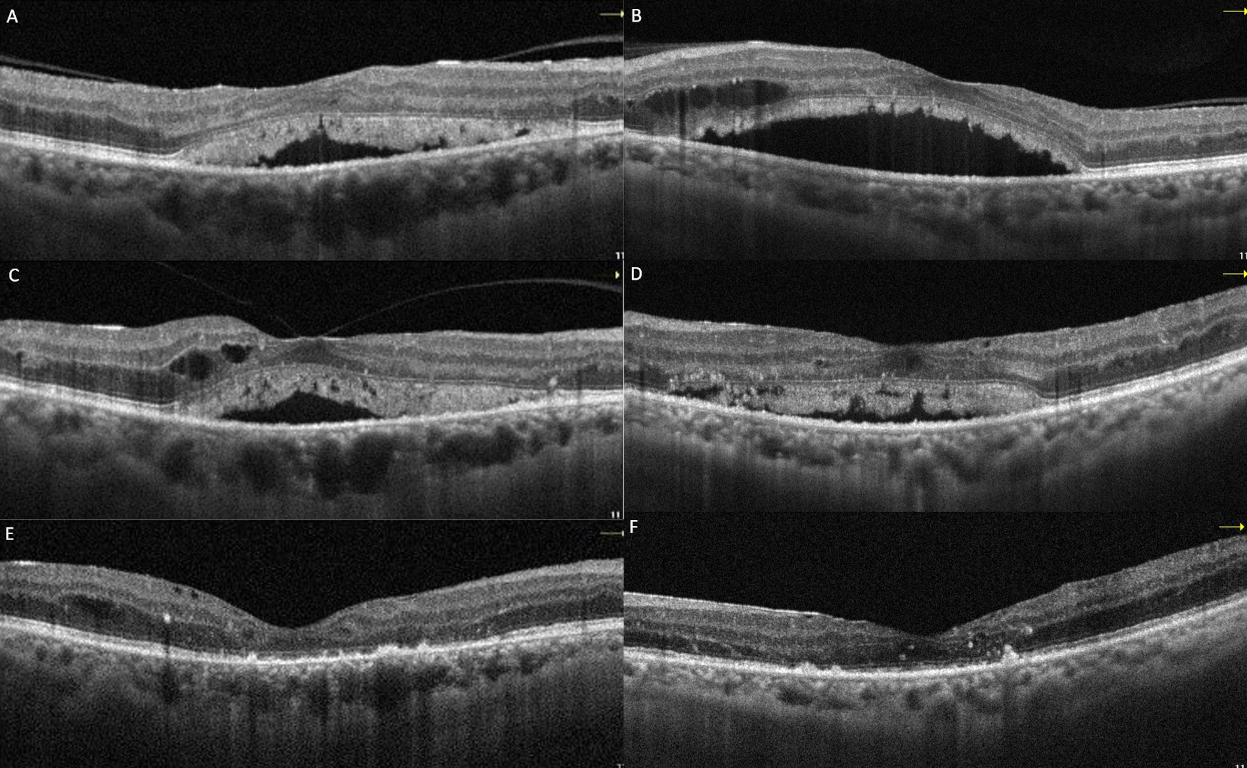

Following three intravitreal bevacizumab injections administered to both eyes, the patient’s BCVA declined to 20/100 in the right eye and 20/60 in the left eye. OCT images showed a decrease in intraretinal fluid, but there was no regression in SRDs (Figure 2A and B [Fig. 2]). Continuing panretinal photocoagulation was scheduled due to retinal ischemia on fundus fluorescein angiography (FFA) (Figure 2C and D [Fig. 2]). However, since the persistence of the SRD, no apparent leakage at the macula on FFA (Figure 2C and D [Fig. 2]), photoreceptor shedding was initiated on OCT (Figure 2A and B [Fig. 2]), and the patient complained of increased weakness and fatigue, an internal medicine consultation was requested. Laboratory tests showed hemoglobulin 6.8 g/dl (normal range: 13.1–17.2 g/dl), albumin 23 g/l (normal range: 35–52 g/dl), erythrocyte sedimentation rate 140 mm/h (normal value: <15 mm/h), C-reactive protein 14.9 mg/l (normal value: <6 mg/l) and hemoglobin A1c 8.1% (normal range: 3.5–5.7%) in the blood sample, and there was +3 proteinuria in the urine. Lymphadenopathy was also detected in the left inguinal region. Abdominal computerized tomography revealed lytic bone lesions in the left iliac wing, right acetabulum and L3–L4 vertebral bodies. The patient was diagnosed with multiple myeloma (MM) based on protein electrophoresis and hematologic examination. He was subsequently started on systemic chemotherapy for MM and no additional injections were administered for macular edema. Following initiation of treatment, macular subretinal fluid gradually resolved bilaterally (Figure 3A–F [Fig. 3]). The final OCT examination, 1 year after the first presentation showed resolution of the serous macular detachment (Figure 3E and F [Fig. 3]). At that time BCVA was 20/80 in the right eye and 20/100 in the left eye.

Figure 3: Macular OCT images of case 1 at 1 month (A: right, B: left), 3 months (C: right, D: left), and 1 year (E: right, F: left) after the initiation of systemic chemotherapy showed resolution of the subretinal fluid and shed photoreceptors.